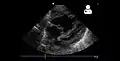

Echocardiography

If pulmonary hypertension is suspected based on the above assessments, echocardiography is performed as the next step.[12][15][56] A meta-analysis of Doppler echocardiography for predicting the results of right heart catheterization reported a sensitivity and specificity of 88% and 56%, respectively.[58] Thus, Doppler echocardiography can suggest the presence of pulmonary hypertension, but right heart catheterization (described below) remains the gold standard for diagnosis of PAH.[12][15] Echocardiography can also help to detect congenital heart disease as a cause of pulmonary hypertension.[12]

- 4-month-old with pulmonary hypertension as seen on ultrasound[59]

4-month-old with pulmonary hypertension as seen on ultrasound[59]- Long standing pulmonary hypertension[60]